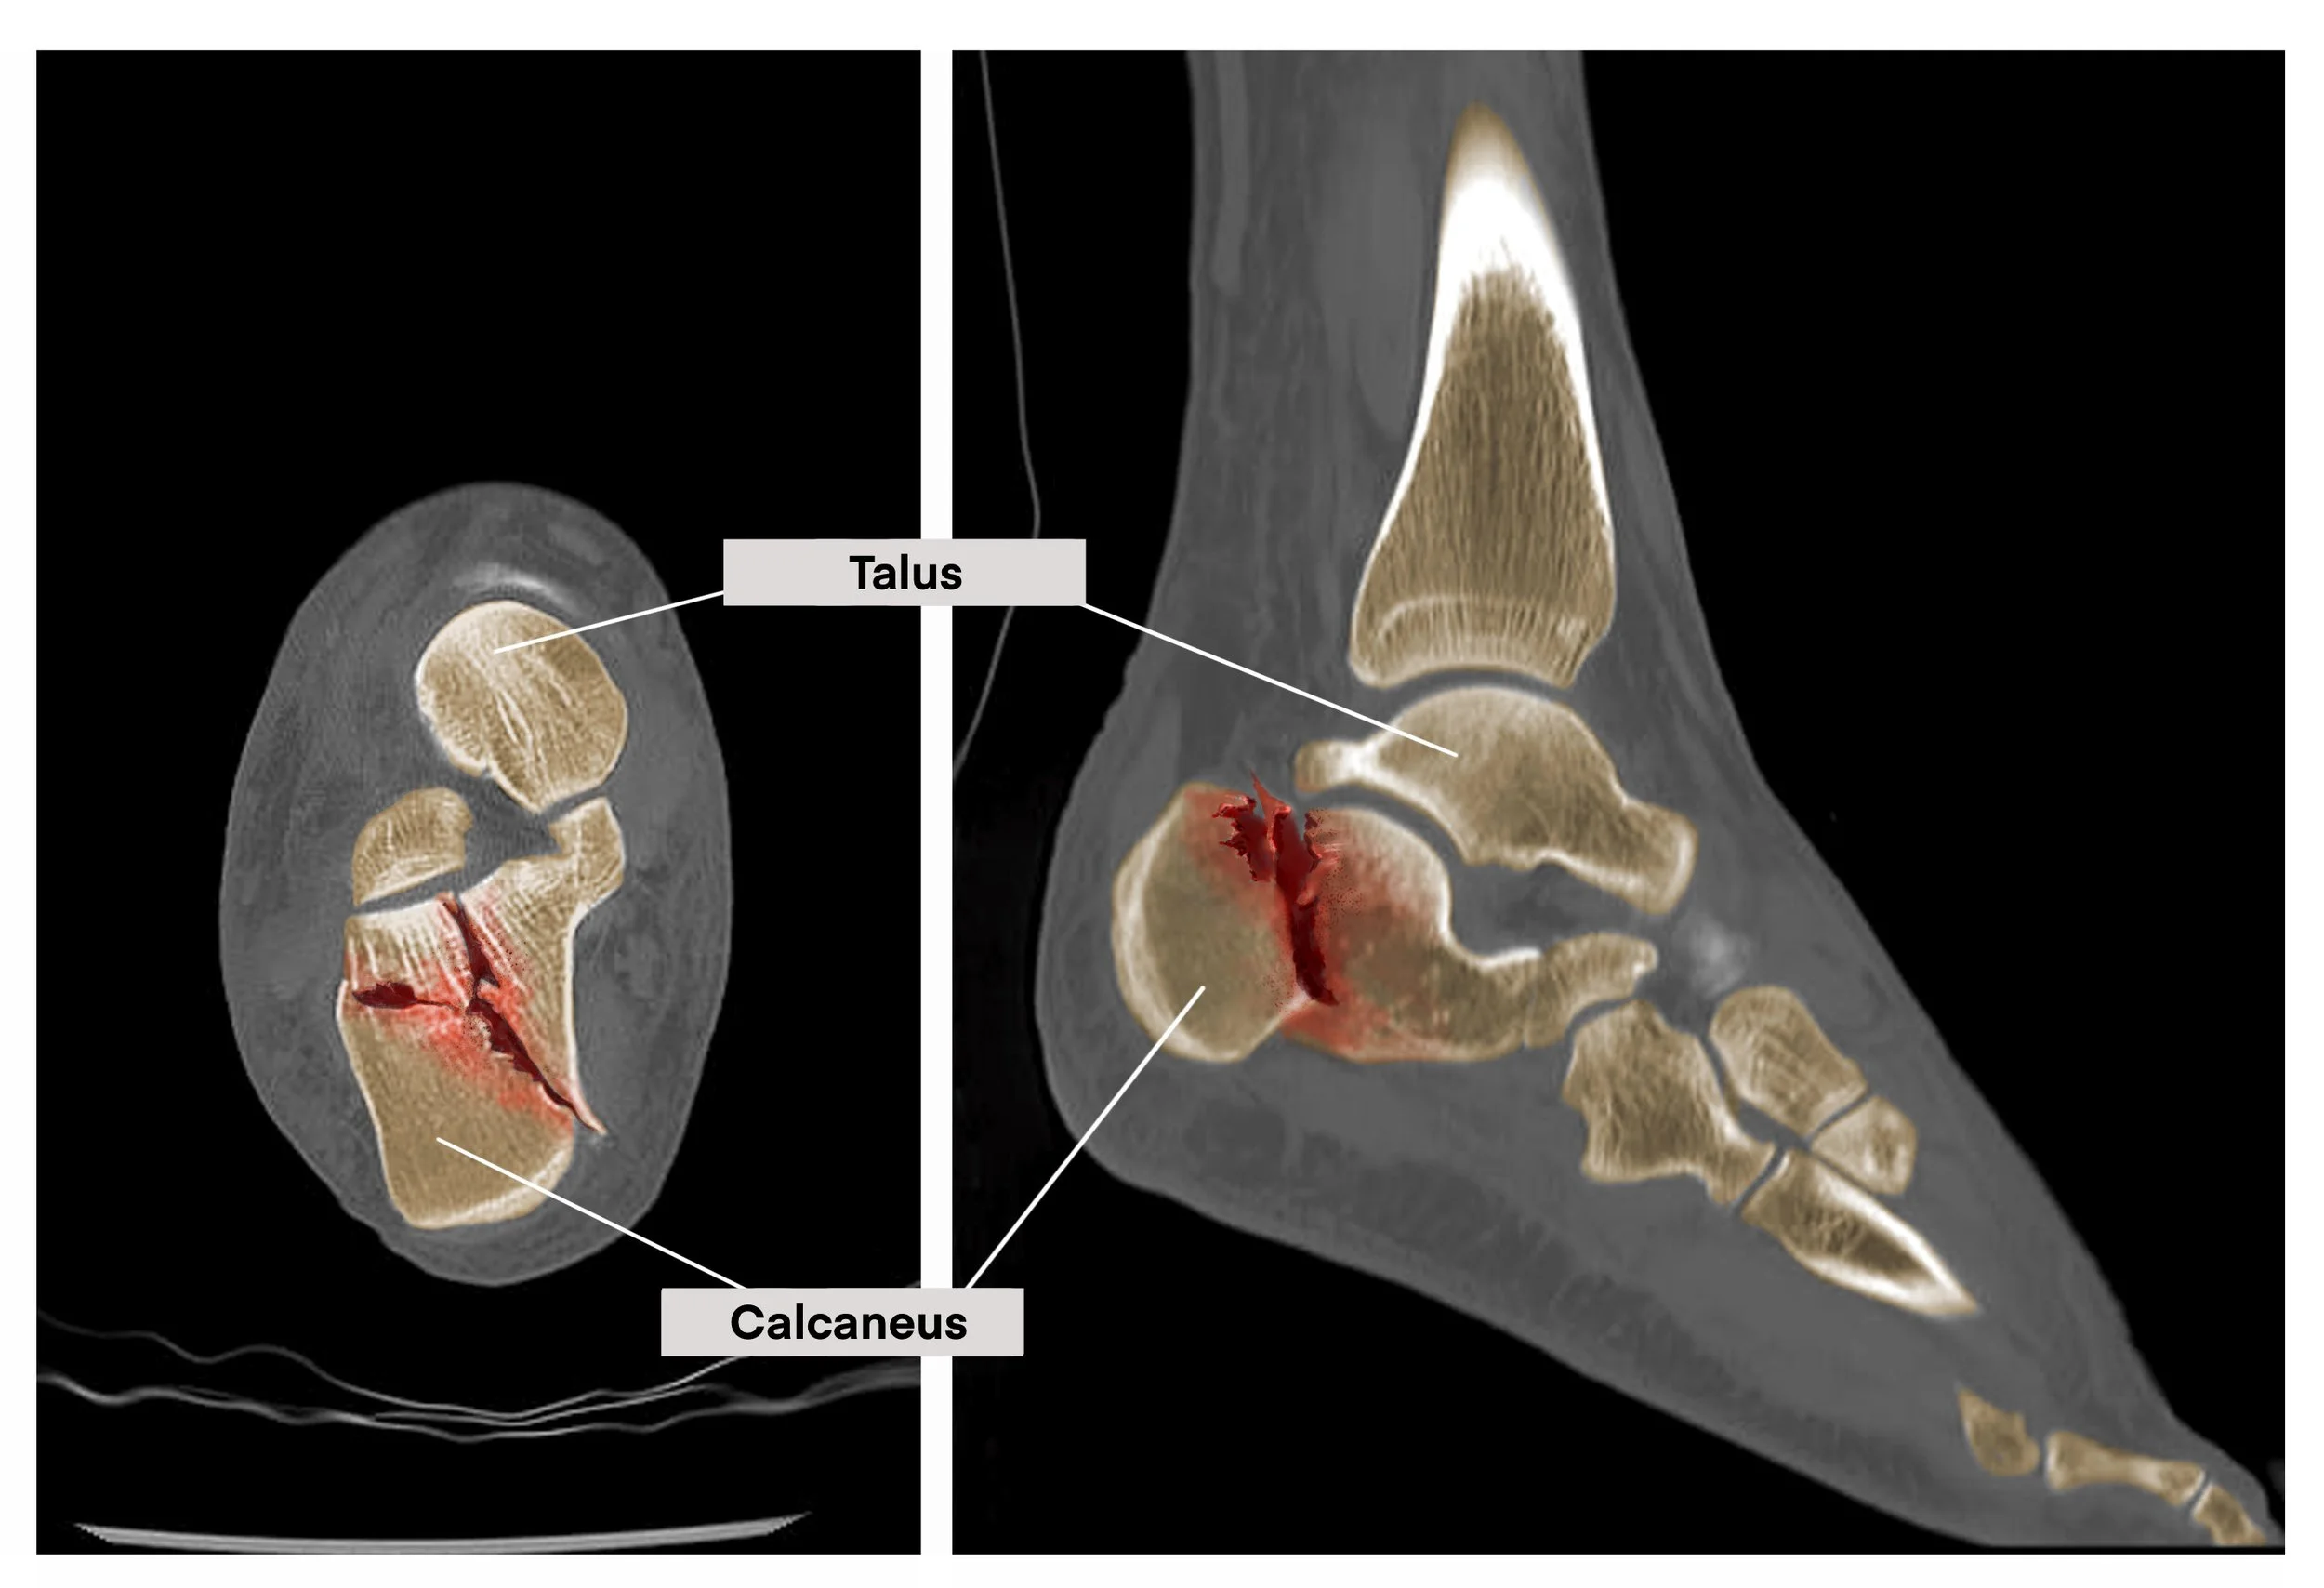

Shattered calcaneus x-ray colorization